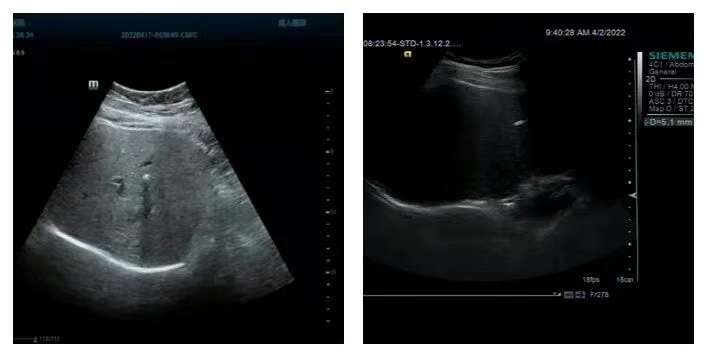

1 .肝内钙化灶

指在彩超或CT图像上肝脏内出现类似结石一样的强回声或高密度影像,在20~50岁的人群多见,男女出现率均等,一般为单个钙化灶,右肝多于左肝,很少同时出现左右肝钙化灶。形成肝内钙化灶的病变很多,包括

①肝内胆管结石,是最常见的因素;

②肝内慢性炎症或创伤;

③寄生虫感染;

④肝脏良恶性肿瘤和肝内转移瘤钙化;

⑤先天发育形成,子宫内的胎儿有肝内钙化灶形成,常合并先天畸形,发现率为0.057%。

2.肾脏钙化灶

肾脏局部组织变硬、钙化,一般是后天逐渐形成,局部组织反复炎症造成钙物质沉积及各种原因所致。钙化灶是检测到的肾内的钙质沉积,一般不能自行消失,只有少量可以被组织吸收。若不继续发展或发生病变一般不会造成其他的影响。肾钙化灶要定期检查,多数情况下,肾钙化灶只是人体细胞坏死之后产生的一些特殊的变异,人体每天都在进行新陈代谢,一些细胞坏死是正常现象,坏死之后,自身循环不畅,从而沉着下来,形成钙化斑,在彩超下显示出类似于结石的亮点。